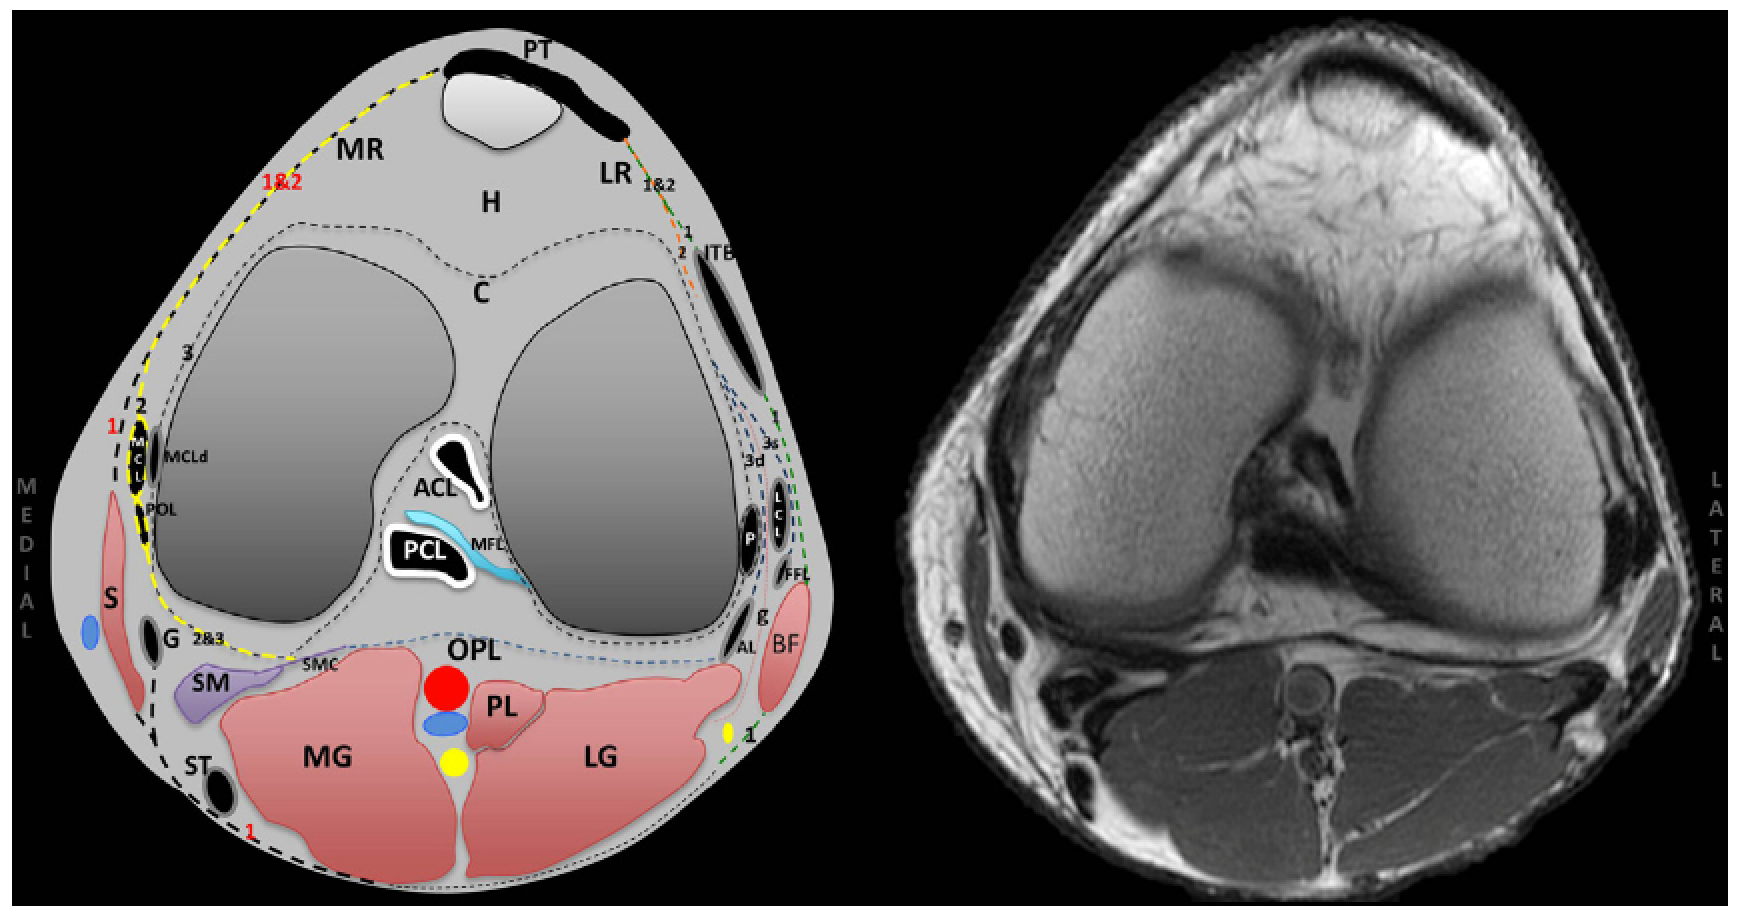

Posterolateral (PLC) and posteromedial (PMC) corners of the knee represent complex anatomic regions because of intricate soft tissue and osseous relationships in small areas. Concise knowledge of these relationships is necessary before approaching their evaluation at imaging. Magnetic resonance imaging offers an accurate imaging diagnostic tool to establish normal anatomy and diagnose and characterize soft tissue and osseous injury. It is important to carefully evaluate the PLC and PMC structures on magnetic resonance imaging before planned surgical intervention to avoid potential complications resulting from occult injury.